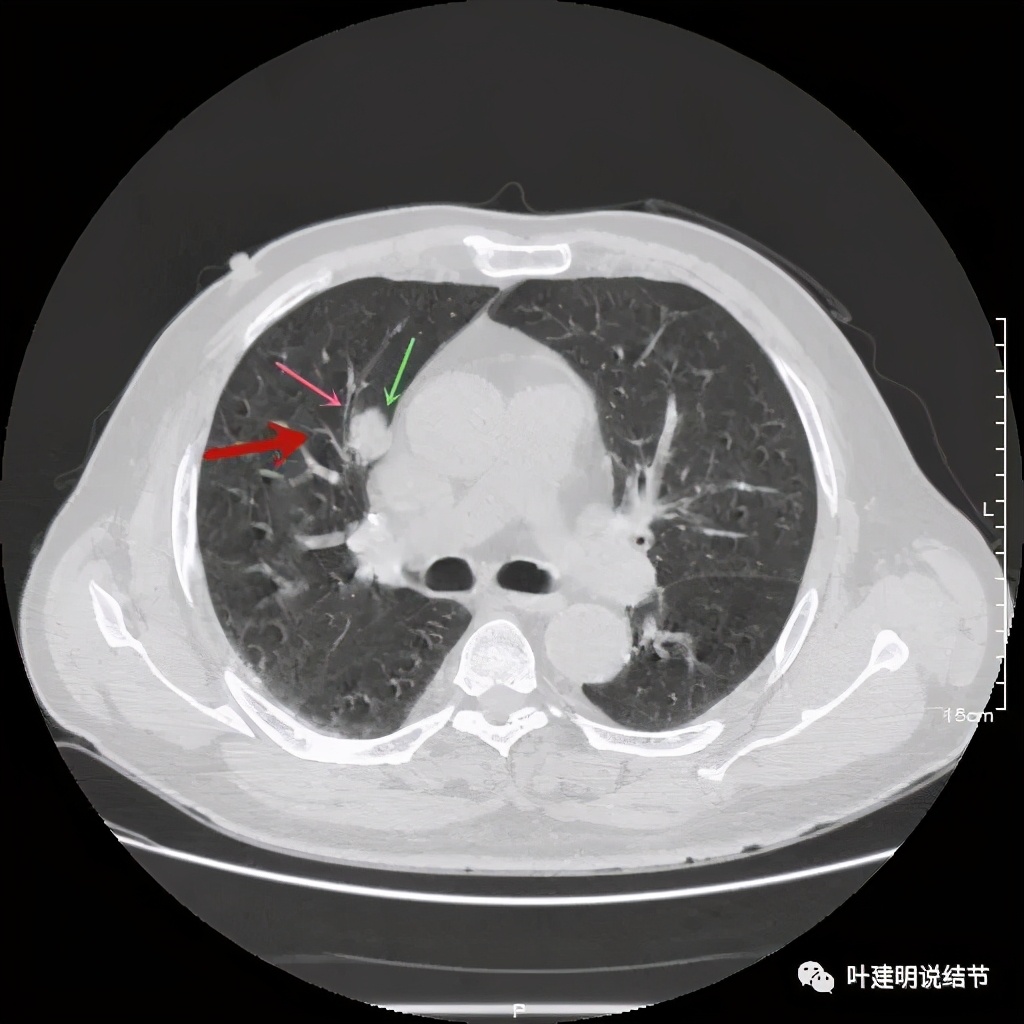

以上几图也示病灶边缘过光(绿色);血管贴边,感觉没受侵犯(桔色)

事前来看,达2.4厘米的不均质实性肿块,增强有轻度不均匀强化,血管贴边走行,支气管疑有截断,恶性不能除外,而且可能性较大。但现在经过手术已已经证实是错构瘤的情况下,我们回头来看,其实有许多不符合恶性的地方:

1、病灶的每个层面,边缘都过于光滑了。肺癌一般到这个大小总要有棘突、分叶、毛刺、牵拉周围胸膜等边缘异常的征象;

2、肿瘤大于2厘米以上,又紧贴血管,多有血管走行异常、受侵或血管进入等征象;

其实我们发现,包括今天这例,只要是错构瘤,“边缘非常光滑”是每一像都具备的!虽然有的似有支气管截断、有的似有血管征、有的似有分叶,但总的只要是边缘非常光滑的实性占位,就要想到错构瘤的可能,若有点状钙化密度,更是强烈要考虑。错构瘤如何靠近胸膜,其实可以切开一点肺实质,挤一下,肿瘤就会滚出来。